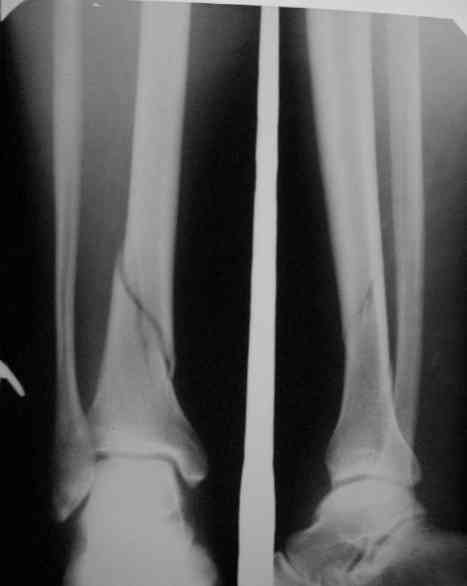

Здравствуйте коллеги!Больной 29 лет поступил 1 мая с Диагнозом: Закрытый спиральный перелом н/3 большеберцовой кости, перелом в/3 малоберцовой.

На пятые сутки выполнен вот такой остеосинтез (см R-gr) . На сегодня мы имеем перелом нижнего винта, замедленное сращение( R- gr от 11.09.06) Больного ничего не беспокоит, ходит с костылями с ограниченной нагрузкой. На наш взгляд возможно обойтись :1 Удаление сломанного винта и верхнего блокирующего с последующим более глубоким погружением штифта и его дистальным блокированием. Либо замена на более длинный (Экперт-Синтез).2 Остеотомия косая малоберцовой кости.С большим вниманием выслушаем возможные варианты, тактики в таком случае.С Уважением Владимир Бахарев.P.S Извинямси за качество снимков!